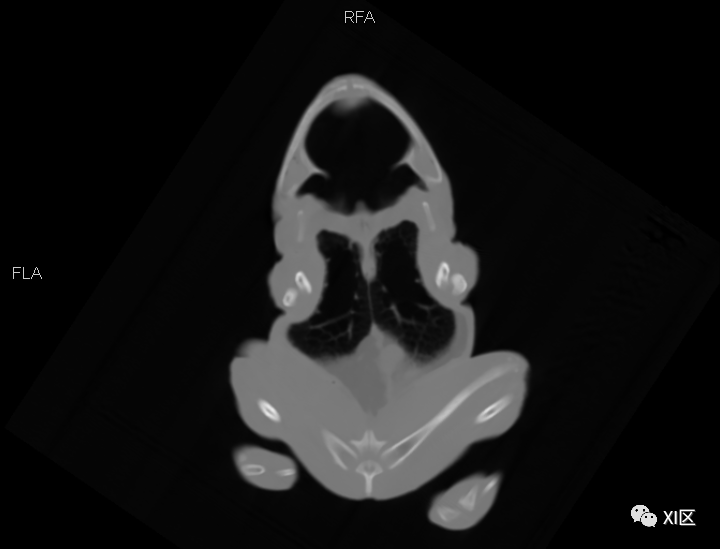

为了了解牛蛙的全身结构

我们给他进行了一次全身CT扫描

并进行了三维重建

我们对牛蛙的体积和密度进行了测量

测量发现

这只牛蛙的体积为292.26ml

平均密度为-106HU

即水的密度的大约0.9倍

(作为对比,人的平均密度约为水的1.02倍)